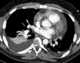

Pulmonary atelectasis

Atelectasis is the collapse or closure of a lung resulting in reduced or absent gas exchange. It is usually unilateral, affecting part or all of one lung. [Source: Wikipedia ]